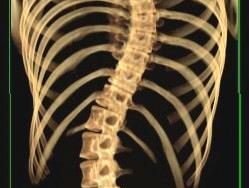

ما هو اعوجاج العمود الفقري؟

اعوجاج العمود الفقري هو انحناء جانبي غير طبيعي في الظهر، يظهر غالبًا في مرحلة الطفولة أو المراهقة أثناء فترات النمو السريع. وقد يكون الانحناء بسيطًا أو متوسطًا أو شديدًا، ويختلف تأثيره من شخص لآخر.

ومع ذلك، من المهم أن نفهم أن اعوجاج العمود الفقري ليس مجرد مشكلة شكلية فقط، بل قد يؤثر على التوازن ووضعية الجسم، وفي الحالات المتقدمة قد يؤدي إلى آلام مزمنة أو صعوبة في الحركة والتنفس.